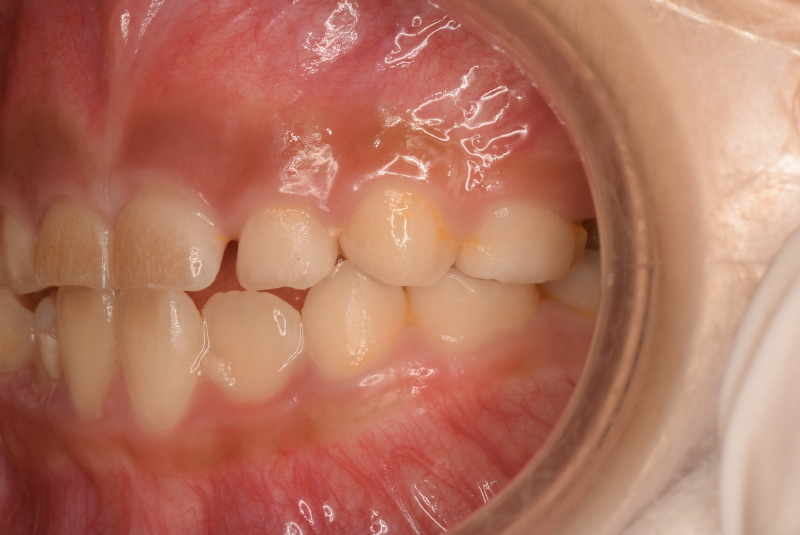

初めに撮った時の写真です。

上の歯と下の歯は噛んでいますが、歯と歯が先端でピッタリ噛んでいます。

先ほどの写真と比べてもらうと上下の歯が当たりすぎています。

最初の頃は上下の歯と歯がぴったりで噛んでいましたが、上の顎の写真の時と同じ日の噛み合わせ写真です。

まだ生えてる途中ですが以前より上下の差があります。